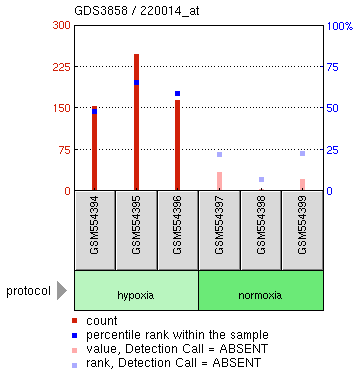

4 – Definitions: hypoxemia, hypercapnea, hypoxia, (an informative/summary figure can be made using Bio-render)

Hypoxia – is a condition involving abnormally low levels of oxygen in body tissues. It can lead to bluish skin, confusion, difficulty breathing, restlessness and fast heart rate. Hypoxia is different to hypoxemia as hypoxia is low oxygen levels in tissues whereas hypoxemia is low oxygen levels in blood.